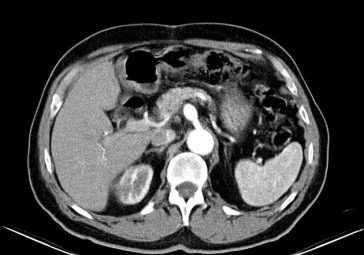

Discovering New Medical Frontiers A Comprehensive Case Report and Literature Review

Reimagining Integrated Healthcare: A Modern Take on Medicine, Nutrition, and Fitness In today’s fast-changing world, our approach to healthcare is evolving rapidly. As an editor with a deep interest in modern medicine, alternative practices, proper nutrition, disease conditions, and fitness, I believe that a more integrated strategy can yield better outcomes for patients and communities […] More